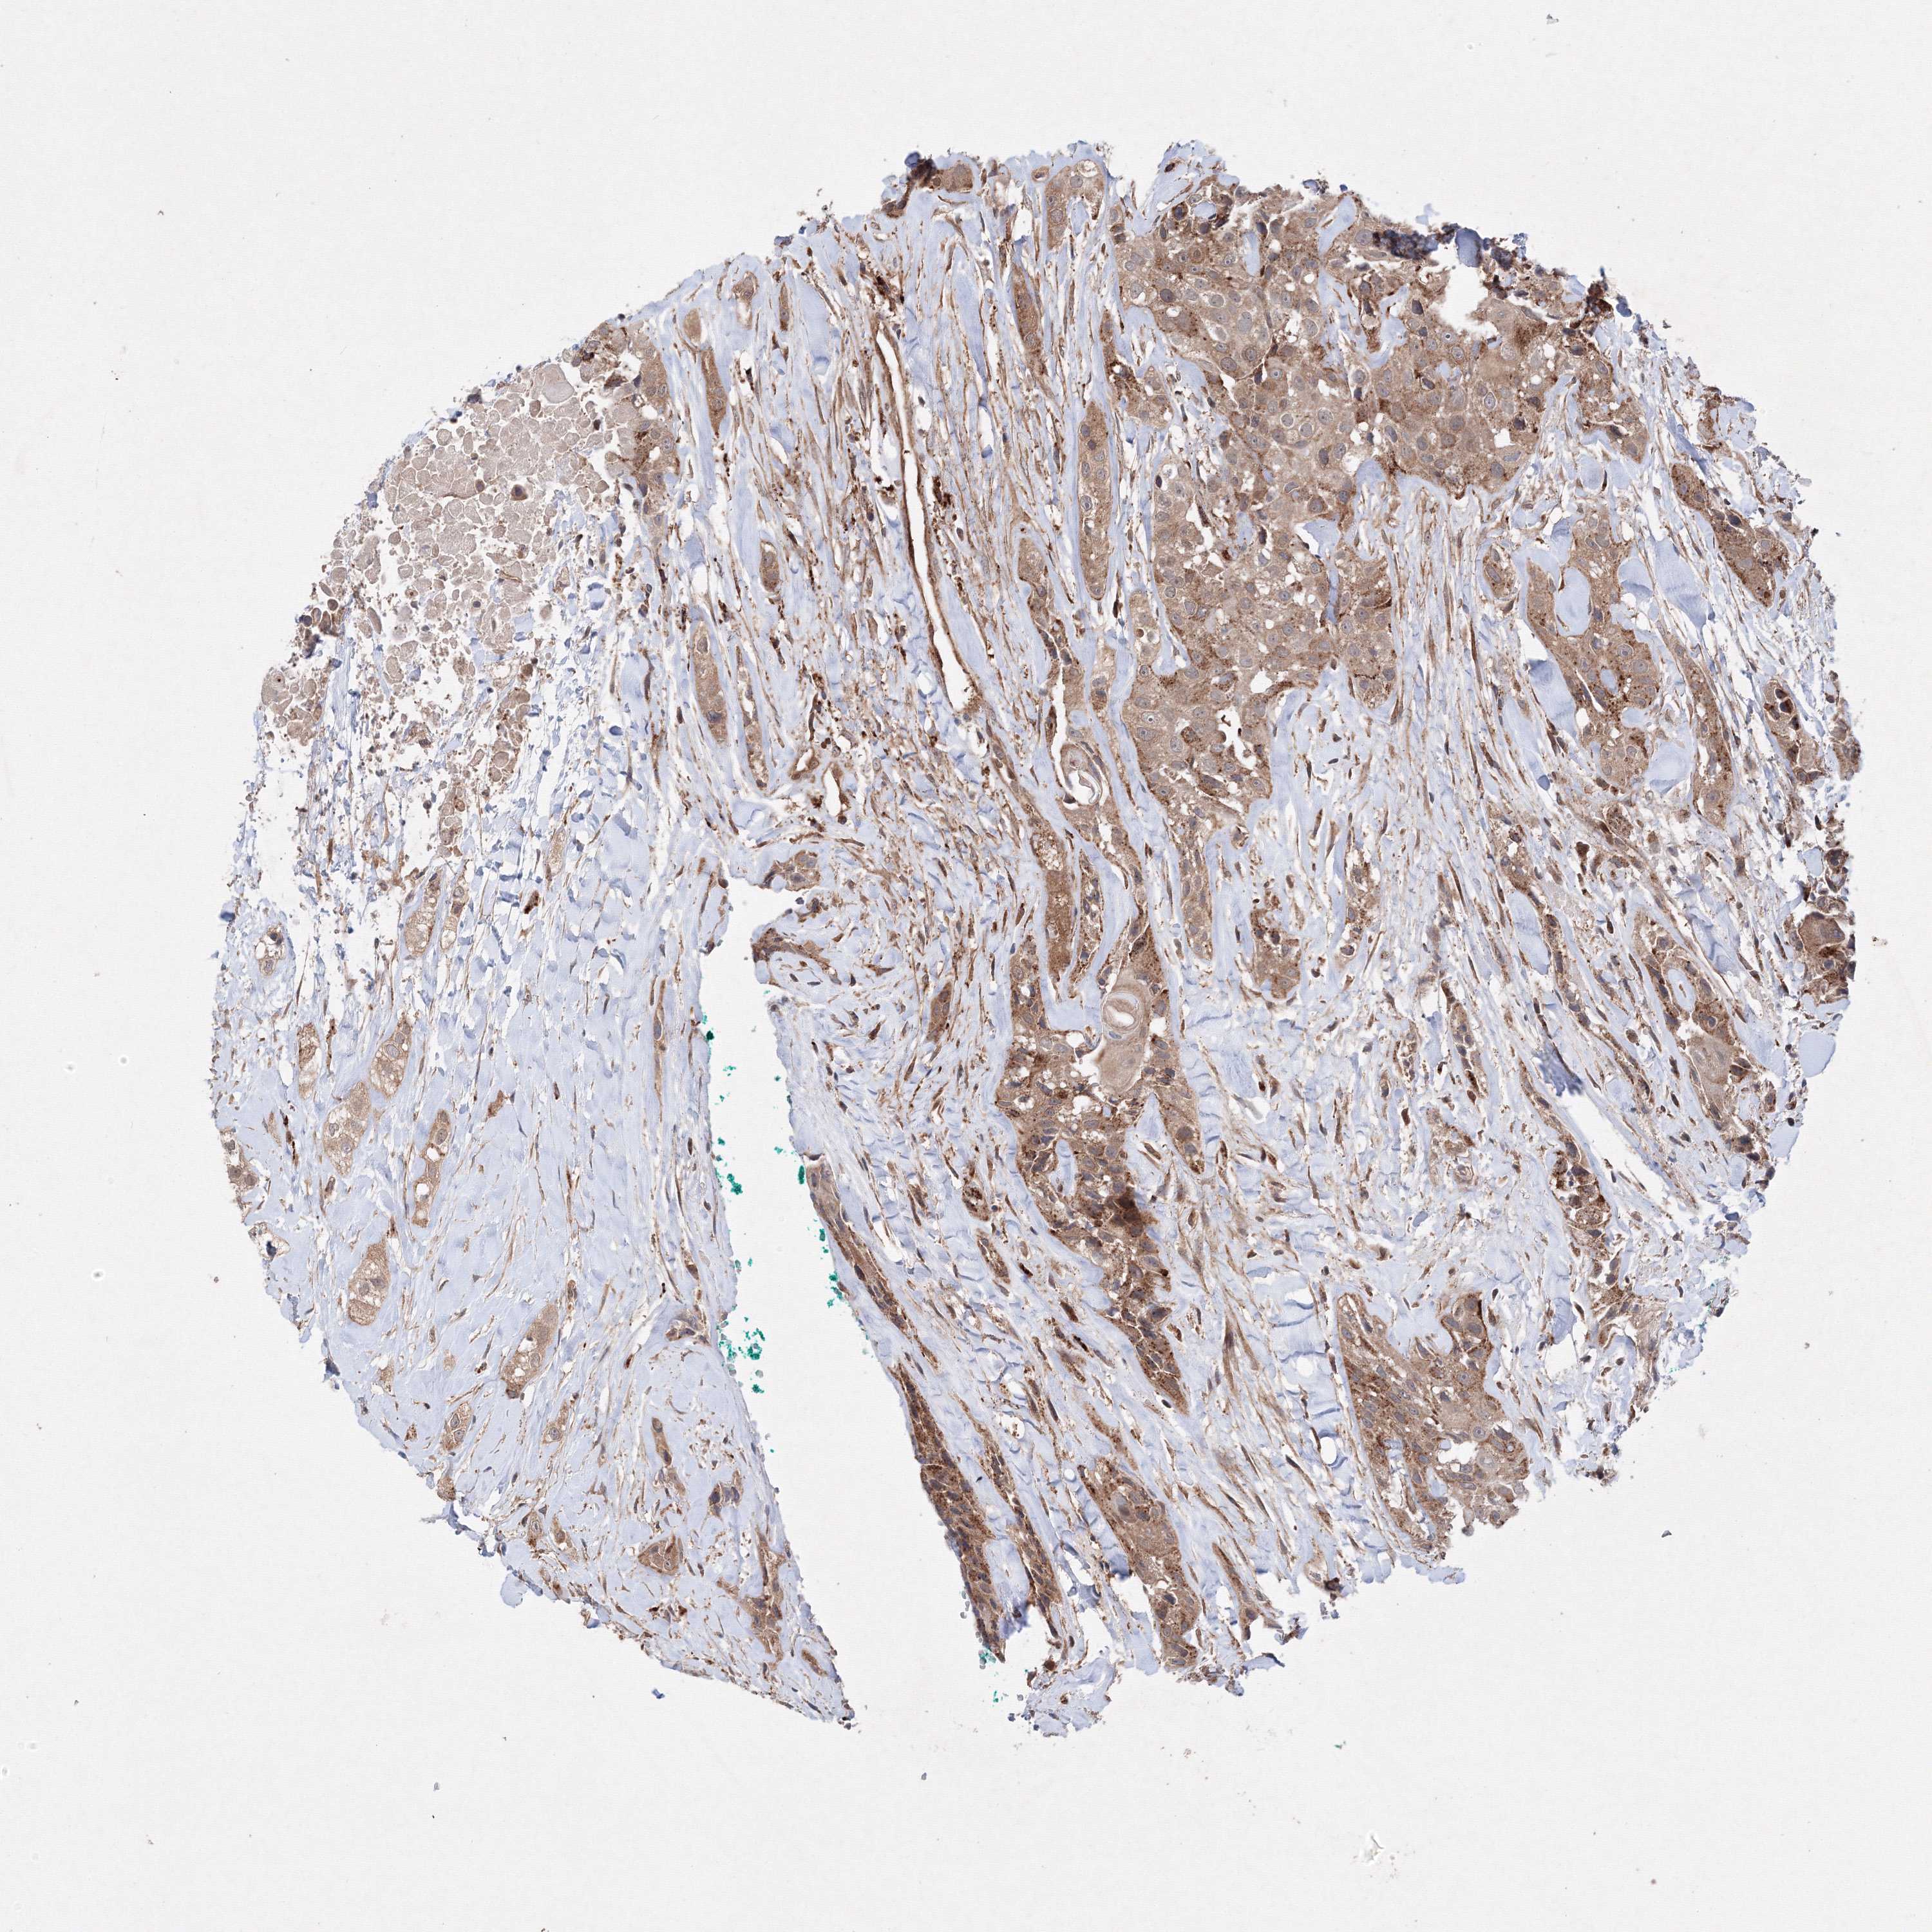

HEAD AND NECK CANCER - Protein expressioni

A mouse-over function shows sample information and annotation data. Click on an image to view it in a full screen mode. Samples can be filtered based on level of antibody staining by selecting one or several of the following categories: high, medium, low and not detected. The assay and annotation is described here.

Antibody stainingi

Antibody staining in the annotated cell types in the current human tissue is reported as not detected, low, medium, or high, based on conventional immunohistochemistry profiling in selected tissues. This score is based on the combination of the staining intensity and fraction of stained cells.

Each image is clickable and will lead to virtual microscopy that enables deeper exploration of all samples and also displays staining intensity scores, fraction scores and subcellular localization as well as patient and tissue information for each sample.

Antibody HPA035894

Staining

High

Medium

Low

Not detected

Intensity

Strong

Moderate

Weak

Negative

Quantity

>75%

75%-25%

<25%

None

Location

Nuclear

Cytoplasmic/membranous

Cytoplasmic/membranous,nuclear

Squamous cell carcinoma, NOS

Squamous cell carcinoma, metastatic, NOS

Adenocarcinoma, NOS